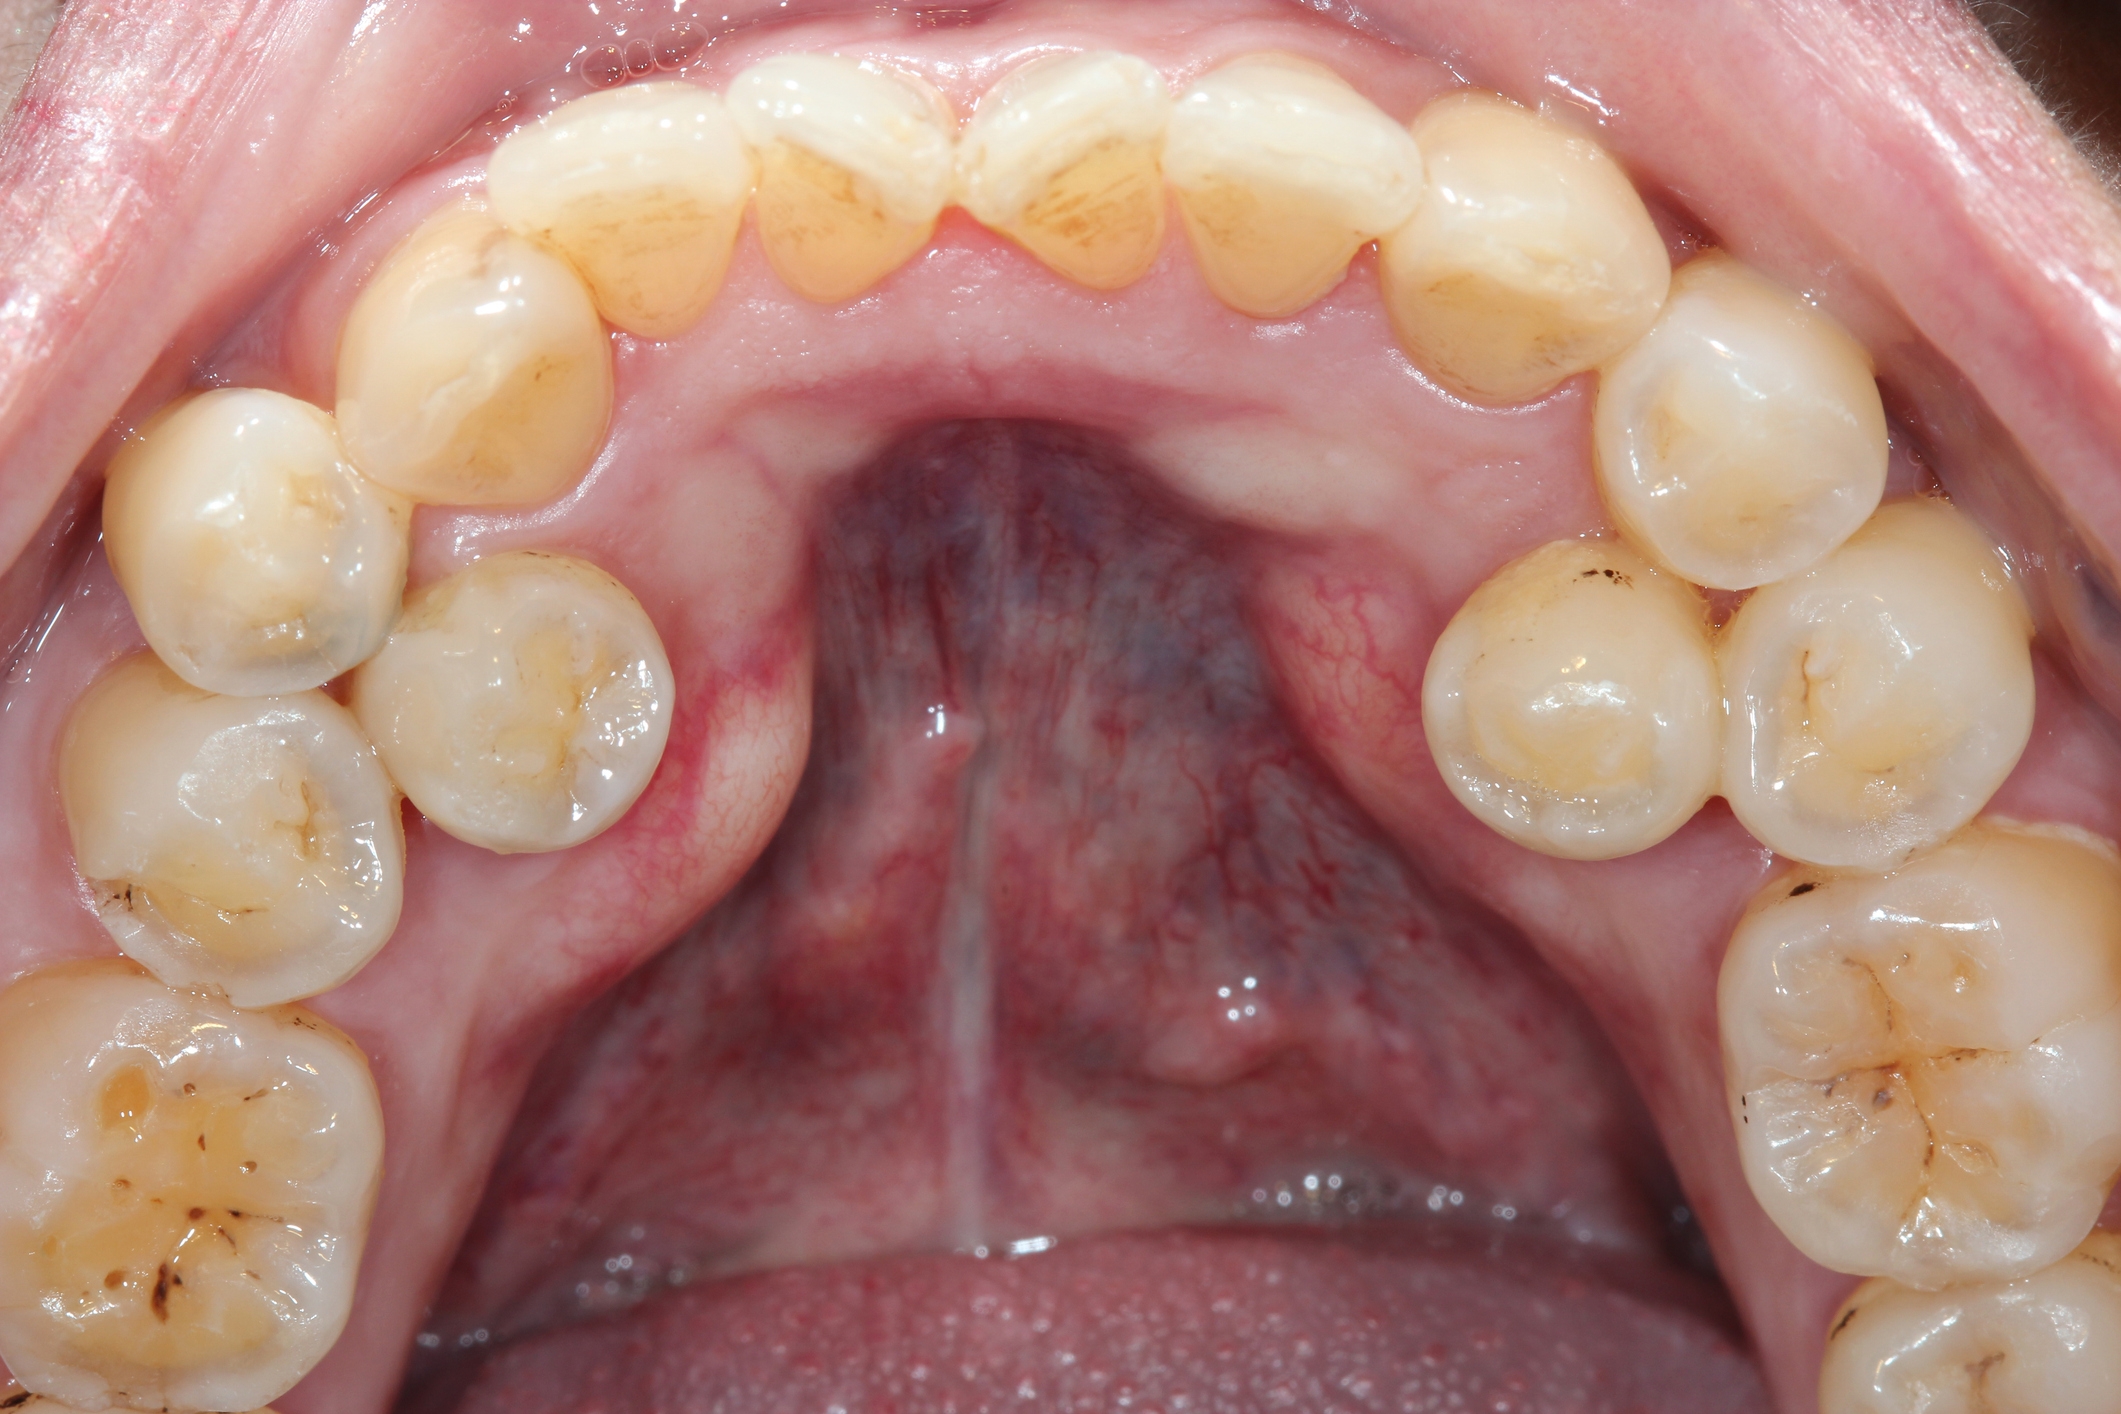

2.I’m sorry to show you this, but this is what’s done to teeth to prep them for veneers.